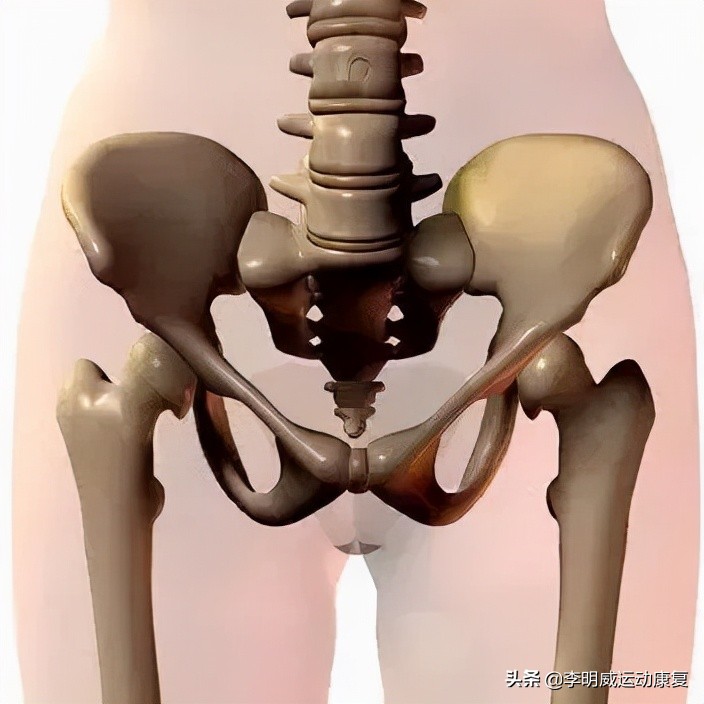

骨盆在身体中间,通过脊柱连接着上半身,成为了脊柱的底座。通过髋关节连接着下半身,与下半身的活动非常相关。因此骨盆是我们人体上一个非常重要的骨骼结构。

首先,骨盆在解剖学上分成了四块大骨头,分别为左右两个髋骨(由髂骨,坐骨,耻骨密合而成),骶骨,和尾骨。

其次,骨盆在运动学上来说又加上了第五节腰椎和骨盆之间的腰骶关节,以及骨盆和股骨之间的髋关节。而髋关节也是人身上活动范围最大的关节之一。